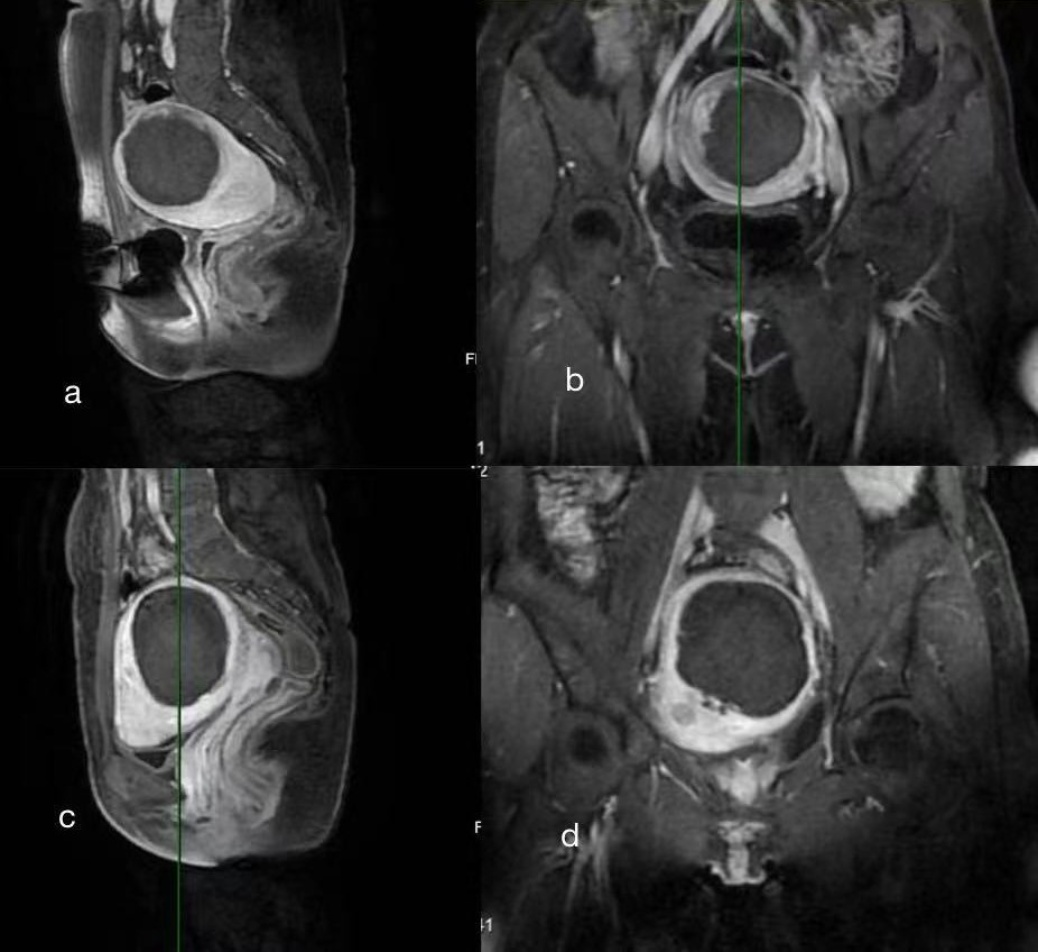

Figure 1. Postoperative MRI comparison between interlayer irradiation ablation mode and layer-by-layer irradiation ablation mode

1. 间层辐照消融模式和逐层辐照消融模式术后MRI对比

图1(a)图1(b)分别为间层辐照消融模式下术后矢状位的冠状位盆腔MRI增强,宫底部肌壁间团块(78 × 68 × 66 mm)呈等/稍短T1、短/稍长T2混杂信号,内部大片无强化区伴边缘小片强化;(c)、(d)分别为逐层辐照消融模式下术后失状位和冠状位盆腔MRI增强,子宫体部后壁肌壁间见边界清晰的短T1、混杂T2信号团块(65 × 74 × 72 mm),增强无强化。两者在影像学上均表现为消融良好。